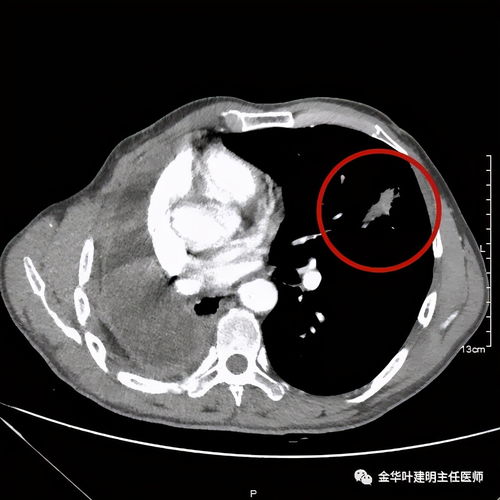

惡性腫瘤細胞由于代謝旺盛而對葡萄糖的需求增加,因此18FDG后,大多數(shù)腫瘤病灶會表現(xiàn)為對18FDG的高攝取,因此可應用18FDG

PET-CT顯像可早期發(fā)現(xiàn)全身腫瘤原發(fā)及轉移病灶,準確判斷其良、惡性,從而正確指導臨床治療決策。但是18F-FDG有著放射性核半衰期,這就總讓受檢者們擔心,做完PET